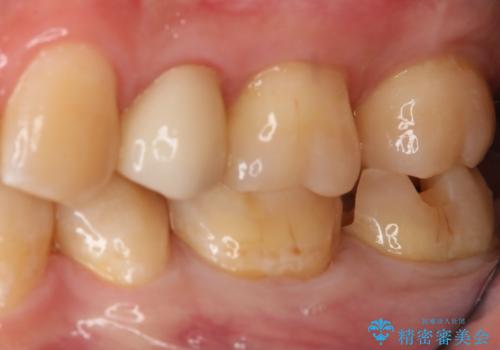

- 左下7番のCR劣化を自費治療にて希望された患者様です。

切削量を考慮してセラミックインレーでの治療を選択しました。

CR直下と隣接面にう蝕が進行していたので、除去した上で形成、印象しています。